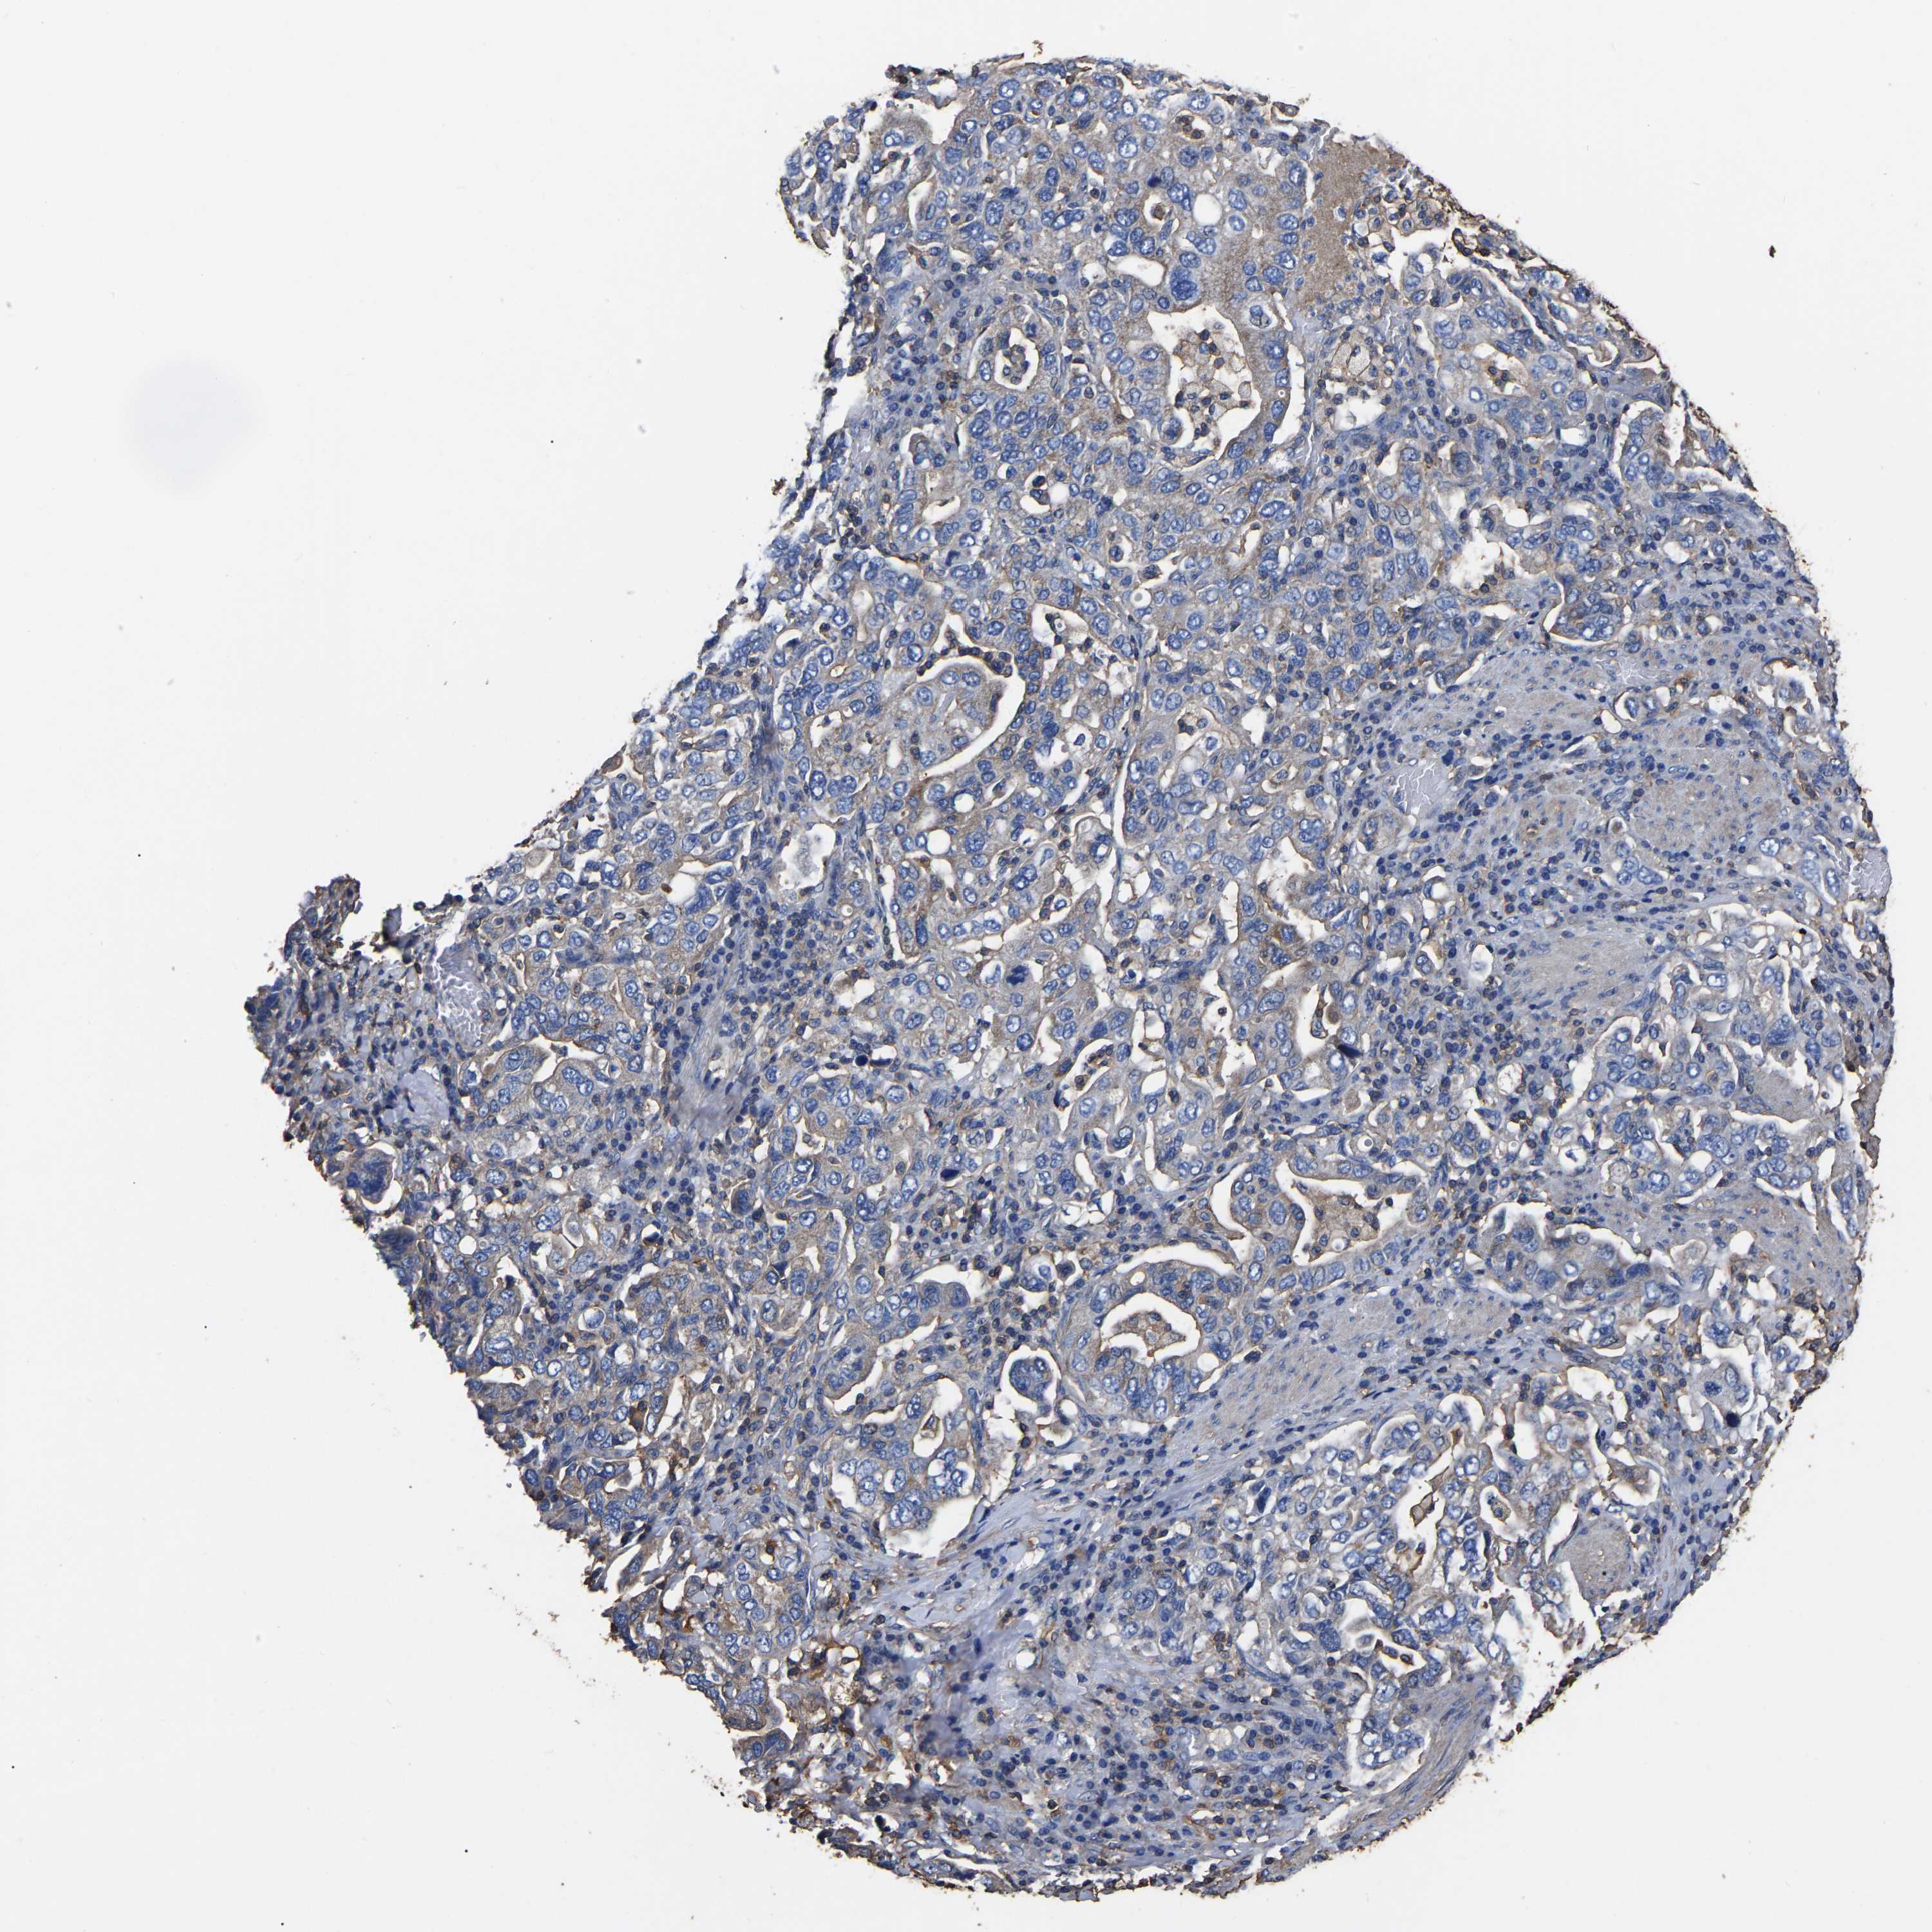

STOMACH CANCER - Protein expressioni

A mouse-over function shows sample information and annotation data. Click on an image to view it in a full screen mode. Samples can be filtered based on level of antibody staining by selecting one or several of the following categories: high, medium, low and not detected. The assay and annotation is described here.

Note that samples used for immunohistochemistry by the Human Protein Atlas do not correspond to samples in the TCGA dataset.

Antibody stainingi

Antibody staining in the annotated cell types in the current human tissue is reported as not detected, low, medium, or high, based on conventional immunohistochemistry profiling in selected tissues. This score is based on the combination of the staining intensity and fraction of stained cells.

Each image is clickable and will lead to virtual microscopy that enables deeper exploration of all samples and also displays staining intensity scores, fraction scores and subcellular localization as well as patient and tissue information for each sample.

Antibody HPA003004

Antibody HPA005819

Staining

High

Medium

Low

Not detected

Intensity

Strong

Moderate

Weak

Negative

Quantity

>75%

75%-25%

<25%

None

Location

Nuclear

Cytoplasmic/membranous

Cytoplasmic/membranous,nuclear

Adenocarcinoma, NOS